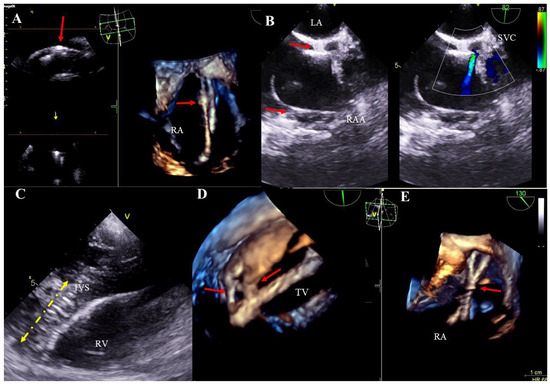

Bacterial vegetations: multi-shaped, irregular, of varying size, balloting formations of heterogeneous echogenicity. Vegetations are diagnosed if there are signs of a generalized infection (positive inflammation markers, blood cultures) or local infection (generator pocket infection) (Figure 2A–D, Movie S4).

Figure 2. TEE images (2D, 3D) showing vegetations on CIED leads. Various-shaped structures representing bacterial vegetations (blue circles) are visualized on the leads (yellow arrow) in the right atrium. D TEE (A,C), 3D TEE (B,D).

Figure 3. TEE (2D, 3D) showing scar tissue around the leads. Segmental thickening of the leads and lead-on-lead adhesions in the right atrium (red arrow) (A). Pathological attachment of the two leads to the interatrial septum and to the atrial wall near the atrial appendage (red arrows). The narrowing of the vena cava at entry into the atrium is caused by the thickened leads and pathological scar tissue (Doppler color) (B). Thickened ventricular lead (yellow line) pathologically attaches to the endocardium of the interventricular septum in the right ventricle (C). The image from the right ventricle depicts a pathological adhesion (red arrows) of the lead to the edge of the tricuspid valve leaflet (D). Binding and intersection of thickened leads in the atrium (red arrow) (E).